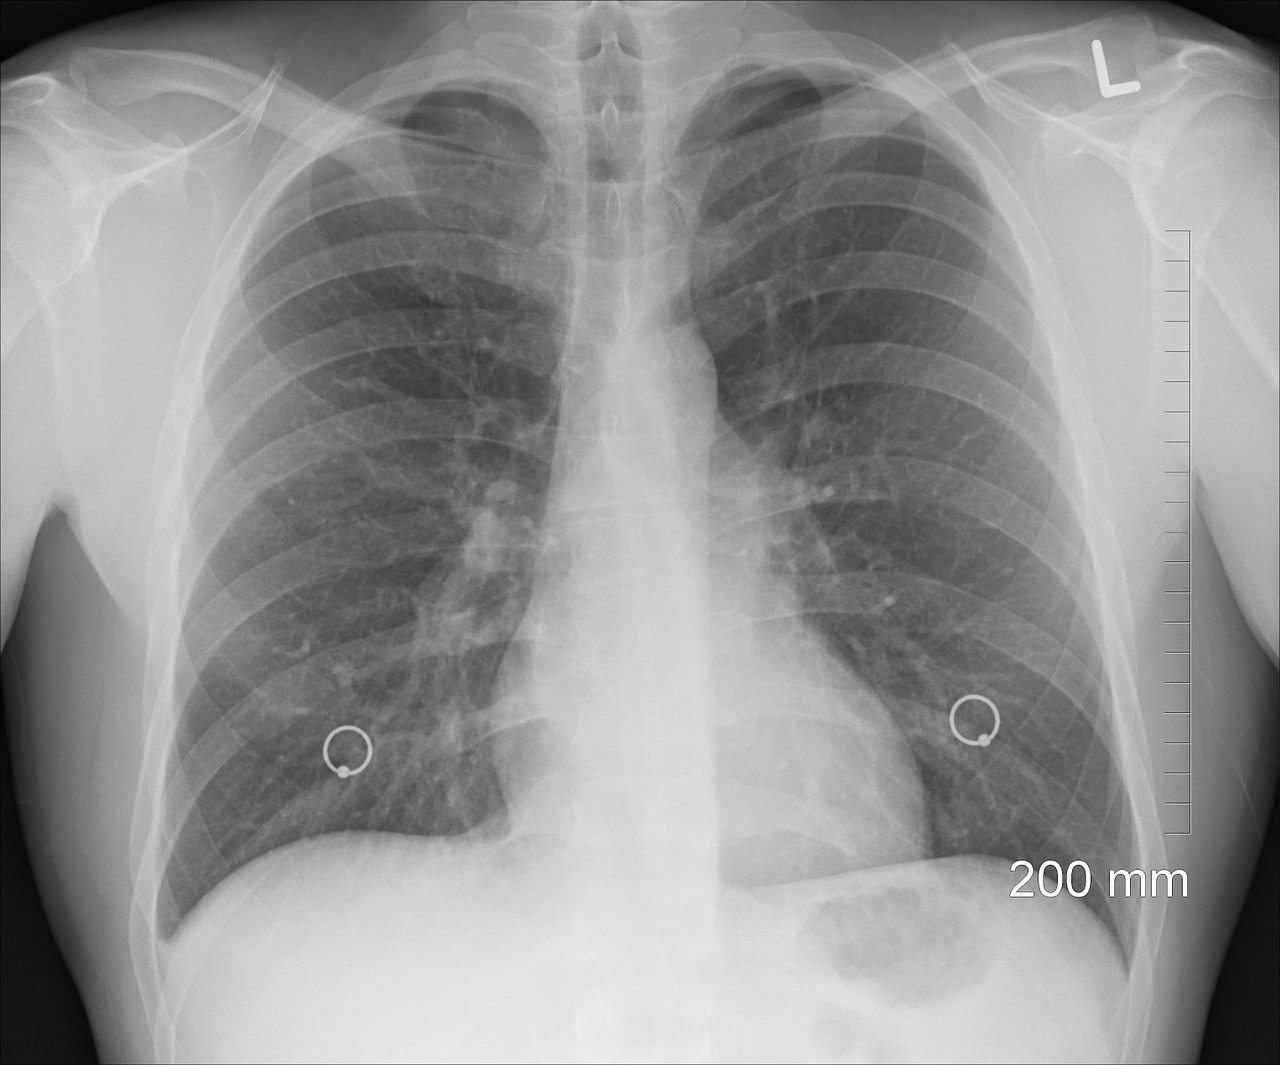

Completamente 300.000 pazienti asmatici ricevono cure mediche in Ungheria e si stima che 150.000 convivano con questa condizione, hanno detto martedì gli esperti.

Ogni anno in Ungheria a 15.000-20.000 pazienti viene diagnosticata l’asma e 15.000-30.000 vivono con asma cronica

Lilla Tamási, pneumologa dell’Università Semmelweis di Budapest, ha dichiarato in occasione della Giornata mondiale dell’asma, aggiungendo che i malati cronici ricevono trattamenti avanzati.

Uno dei problemi principali è che circa il 50% dei pazienti asmatici non assume regolarmente i propri farmaci, il 90% dei quali sono pagati dal fondo nazionale di assicurazione sanitaria, ha affermato Tamási, vicedirettore della Clinica di pneumologia dell’università.